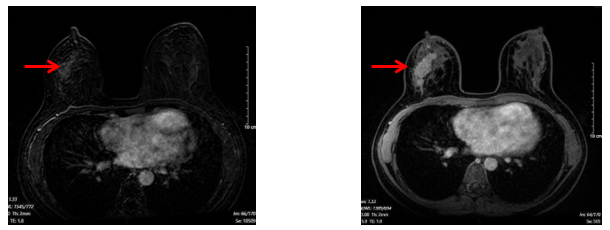

+ Chụp cộng hưởng từ hai bên tuyến vú (03/11/2024)

· Vú phải: vị trí góc 1/4 trên trong có nốt kích thước 5mm ngấm thuốc muộn tăng dần, không thấy thải thuốc.

· Không thấy hình ảnh tụt núm vú, không thấy co kéo da

· Hố nách bên phải, chặng I có vài hạch, có vỏ hạch dày, lớn nhất kích thước 7x13mm